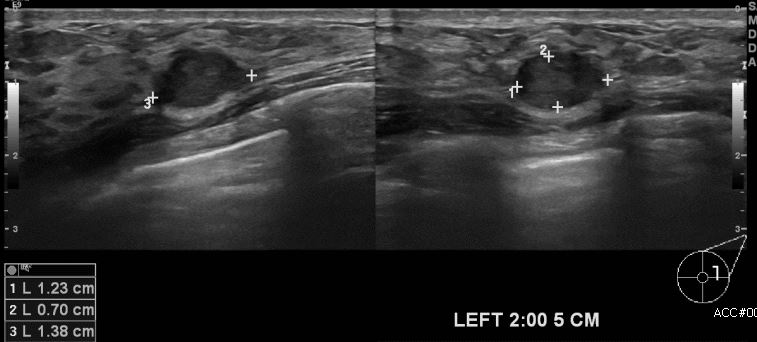

상기환자 건강검진상 이상 소견으로 내원하신 40대 여성분으로 좌측 유방 2시 방향에서 5cm 떨어진 거리의 의심스러운 혹 조직검사 시행하여 좌측 점액성 유방암 진단되었습니다.